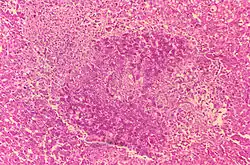

Granuloma and necrosis in the liver of a guinea pig infected with Brucella suis

Brucellosis in humans is usually associated with consumption of unpasteurized milk and soft cheeses made from the milk of infected animals—often goats—infected with B. melitensis, and with occupational exposure of laboratory workers, veterinarians, and slaughterhouse workers. These infected animals may be healthy and asymptomatic.[12] Some vaccines used in livestock, most notably B. abortus strain 19, also cause disease in humans if accidentally injected. Brucellosis induces inconstant fevers, miscarriage, sweating, weakness, anemia, headaches, depression, and muscular and bodily pain. The other strains, B. suis and B. canis, cause infection in pigs and dogs, respectively.[13]